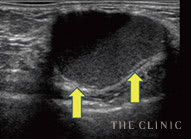

石灰化

被膜にカルシウムの結晶が沈着したしこりはエコーで投影できず、深部が黒く映ります。

瘢 痕

しこりから壊死脂肪が漏れて炎症すると、しこりが瘢痕化。エコー鑑別が難しい症例です。

脂肪注入豊胸後の石灰化したしこり -

脂肪注入豊胸後の瘢痕化したしこり